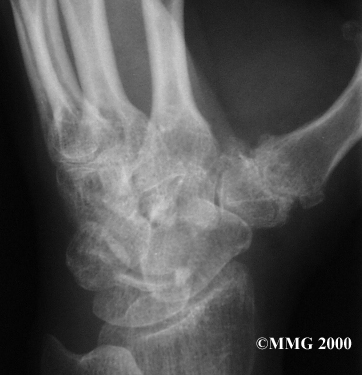

Your doctor may take to see how much the joint is damaged.

This test usually determines how bad the degenerative arthritis has become. How much articular cartilage remains in the joint can be .